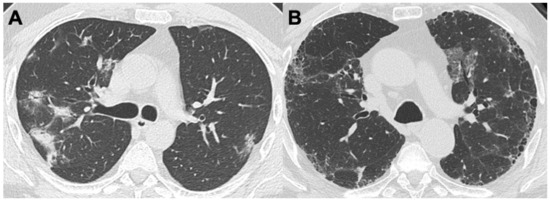

2.4. Microscopic Polyangiitis (MPA)

| MPA | Bronchiectasis (40%) | GGO (23–94%); reticular changes (UIP, NSIP, and DIP patterns); consolidations; diffuse alveolar hemorrhage (25–60%) | Pleural effusion; pleuritis | |